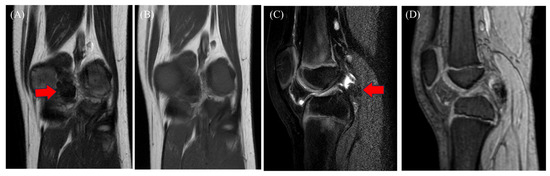

This report describes a rare case of a pediatric tenosynovial giant cell tumor (TSGCT) with a delayed diagnosis. A 9-year-old boy presented with a 3-month history of knee pain and swelling, initially attributed to a femoral non-ossifying fibroma and arthritis based on computed [...] Read more.

This report describes a rare case of a pediatric tenosynovial giant cell tumor (TSGCT) with a delayed diagnosis. A 9-year-old boy presented with a 3-month history of knee pain and swelling, initially attributed to a femoral non-ossifying fibroma and arthritis based on computed tomography findings and slightly elevated C-reactive protein levels. The symptoms persisted despite medical treatment. Magnetic resonance imaging (MRI) revealed a tumor in the posterior compartment. He underwent surgery, and the pathology confirmed the diagnosis of localized TSGCT. Six months postoperatively, the patient remained asymptomatic. Pediatric knee pain is a complex symptom associated with inflammatory conditions and benign and malignant tumors. Benign tumors, as in this case, can be misdiagnosed as arthritis, delaying diagnosis and treatment. MRI is recommended in cases involving symptom persistence. However, histopathological, immunohistochemical, and morphological examinations are crucial for definitive diagnosis, particularly when the imaging findings are inconclusive. Full article